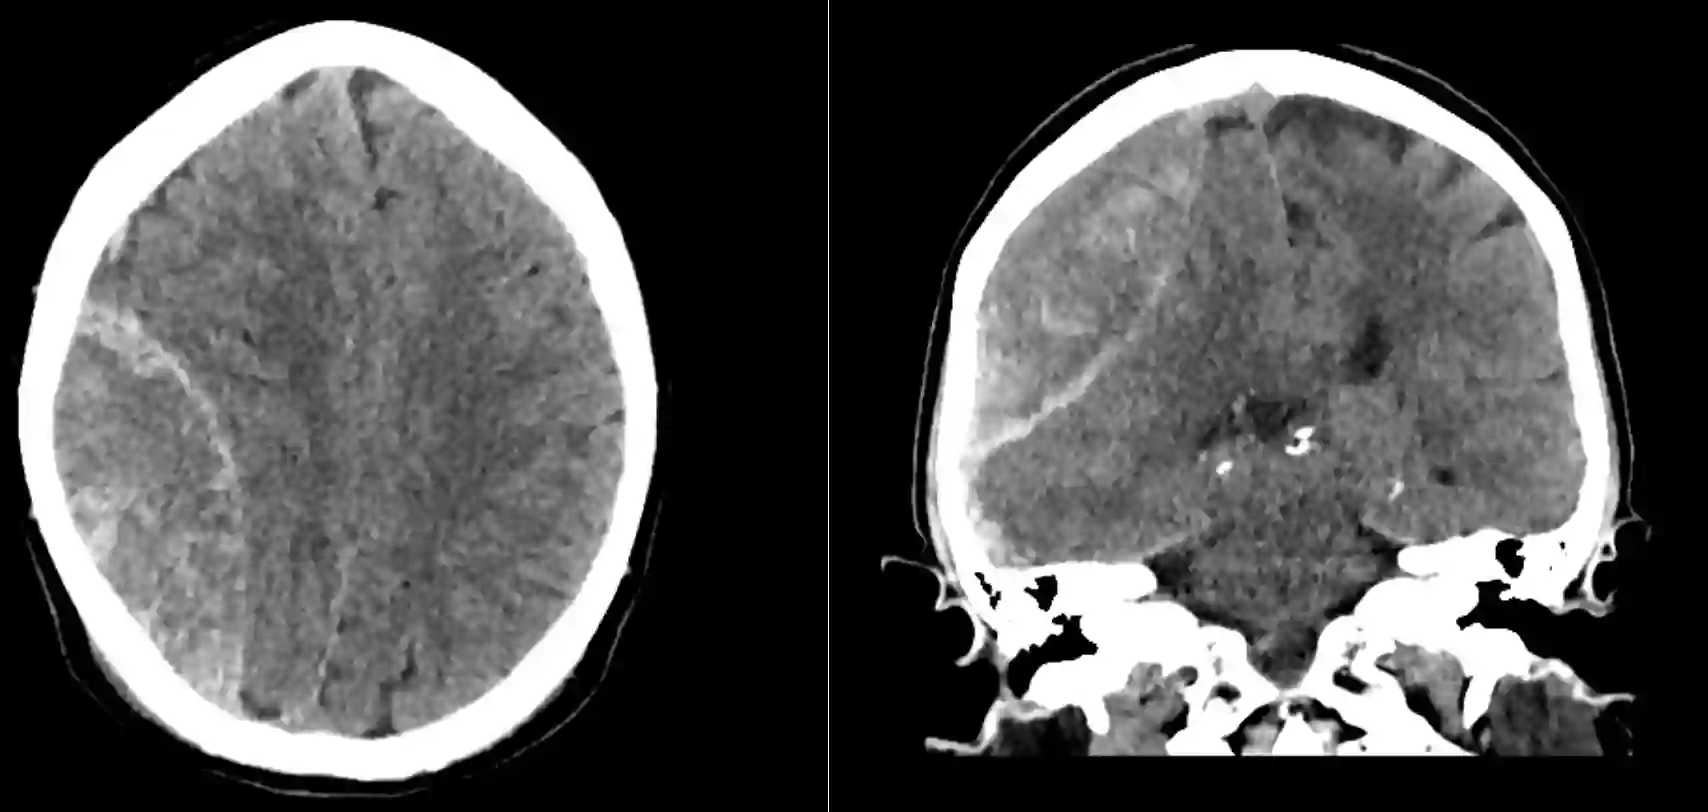

Epiduralhämatom im CT

CT-Bild eines Epiduralhämatoms, welches notfallmässig operiert werden musste.

Darstellung eines großen rechtsseitigen Epiduralhämatoms, welches direkt im Anschluss an die Bildgebung operativ entlastet wurde.